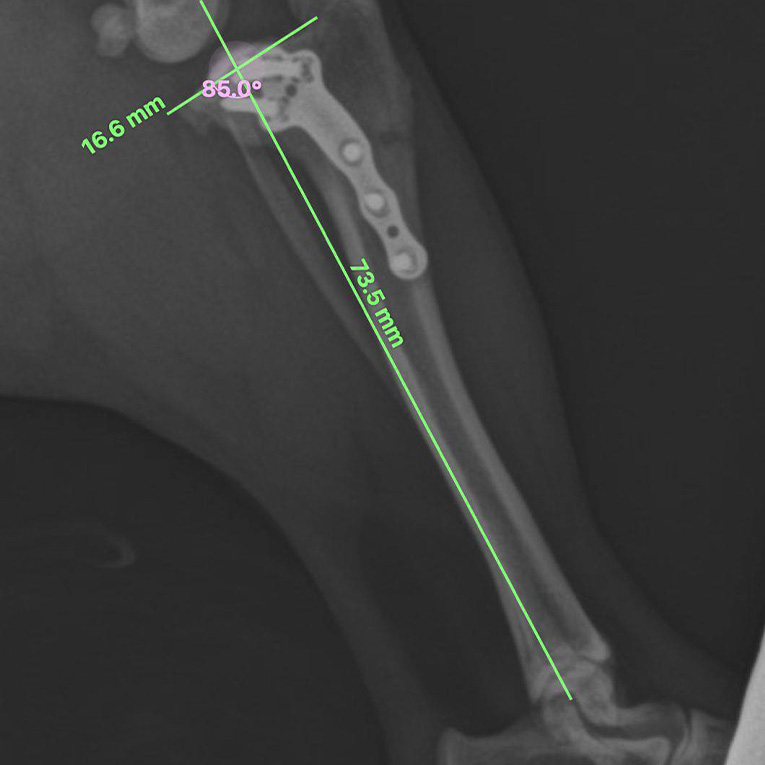

ვეტერინარიუმში ოპერაციის დასაგეგმად კლინიკის მთავარი ვეტერინარი და ქირურგიის განყოფილების უფროსი ლაშა-გიორგი ჯაფარიძე იყენებს ლიცენზირებულ პროგრამას - vPOP PRO (Veterinary Preoperative Orthopaedic Planning). ეს არის მსოფლიოში წამყვანი პლატფორმა ვეტერინარული ორთოპედიული ოპერაციების დაგეგმვისთვის. იგი საშუალებას იძლევა ზუსტად განისაზღვროს მოტეხილობების ხასიათი, ძვლების ზომები, შეირჩეს ოპტიმალური იმპლანტები და წინასწარ შეფასდეს ოპერაციის სავარაუდო შედეგები.

იზის დაუდგინდა წინა ჯვარედინი იოგის (cranial cruciate ligament) სრული გაწყვეტა და მას აღენიშნებოდა მე-5 ხარისხის კოჭლობა.

წინა ჯვარედინი იოგის გაწყვეტის ერთ-ერთ ყველაზე ეფექტურ და თანამედროვე მკურნალობის მეთოდად ითვლება ქირურგიული ჩარევა - დიდი წვივის ნიველირებადი ოსტეოტომია (TPLO - Tibial Plateau Leveling Osteotomy). ეს მეთოდი საერთაშორისოდ ოქროს სტანდარტად არის აღიარებული და ხასიათდება მაღალი (90-95%) წარმატების მაჩვენებლით. იგი ძაღლს სრულფასოვან მოძრაობის ფუნქციას უბრუნებს და მნიშვნელოვნად აუმჯობესებს ცხოვრების ხარისხს.